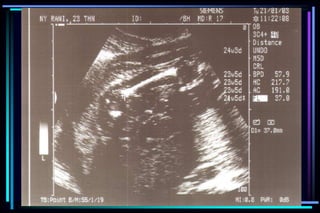

gestational age

 Crown Rump Length (CRL)

 Biparietal diameter (BPD)

 Femur Length (FL)

 Head Circumference (HC)

 Abdominal Circumference (AC)

Accuracy of ultrasound measurement for

different gestational groups

Ultrasound parameter Accuracy

 Gestational sac diameter + 7 days

 Crown Rump Length + 3-5 days

 BPD second trimester + 1 to 1.5 weeks

 BPD third trimester + 2 to 4 weeks

 FL second trimester + 1 to 1.5 weeks

 FL third trimester + 3 to 3.5 weeks

 Multiple parameter (2nd trimester) + 1.5 weeks

 Multiple parameter (3rd trimester) + 2.5 weeks